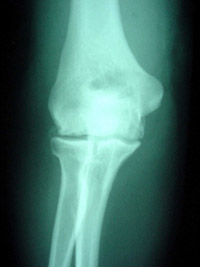

X-ray showing an elbow with early degenerative changes.

A doctor can usually diagnose osteoarthritis of the elbow based on symptoms and standard X-rays. X-rays show the arthritic changes. Advanced diagnostic imaging, such as CT (computed tomography) or MRI (magnetic resonance imaging), is typically not needed to diagnose osteoarthritis of the elbow. Elbow osteoarthritis that occurs without previous injury is more common in men than women. Onset typically occurs in patients 50 years of age or older, but some patients can have symptoms earlier.